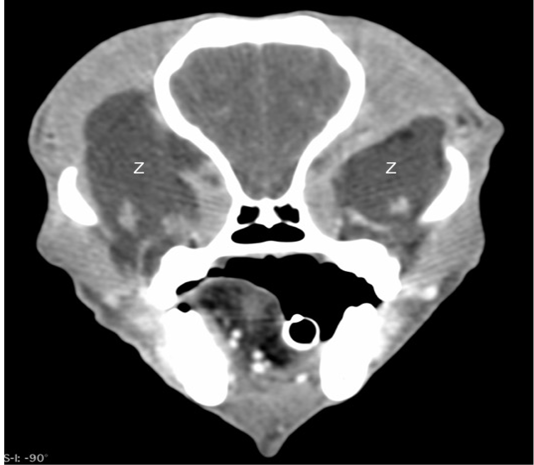

Figure 3

Post-contrast computed tomographic image in a soft tissue window showing the bilateral retrobulbar masses (Z) to have no enhancement.